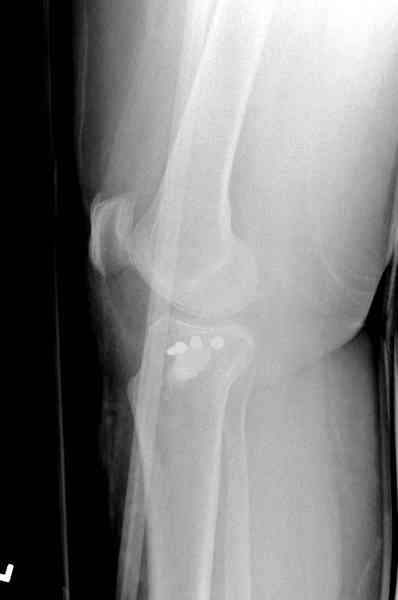

Здравствуйте, уважаемые коллеги!Подскажите, пожалуйста, какой выбрать доступ и способ фиксации при импрессионном переломе заднего отдела наружного мыщелка большеберцовой кости. Женщина 40 лет, травму получила 02.01.2008, катаясь на горных лыжах.Есть ли здесь необходимость использовать задний доступ, или можно справиться через наружный? Есть ли шансы сделать закрыто - под ЭОП через медиальное "окошко" поднять забойником суставную поврехность? Какой лучше использовать фиксатор?Спасибо.

Из медиального окна можно приподнять латеральную

импрессию. Фиксация тремя параллельными шурупами в

эпифизарной части над импрессией. Создается крыша,

которая предупредит коллапс. На образовавшуюся полость - костная пластика из аутокости или синтетический заменитель. Мы применяем Osteoset в 4-5 мм диаметре таблеточки или иньекционную форму Prodens.

Медиально, обычно на протовоположной

строне, делается окно в кортикальном слое, кривым забойником под рентгеном поднимается импрессия.

Это техника применяется, когда имеется

центральная импрессия, а при ипрессии с краевым переломом - после приподнимания импрессии опорная (Butress) пластина, как на снимке.